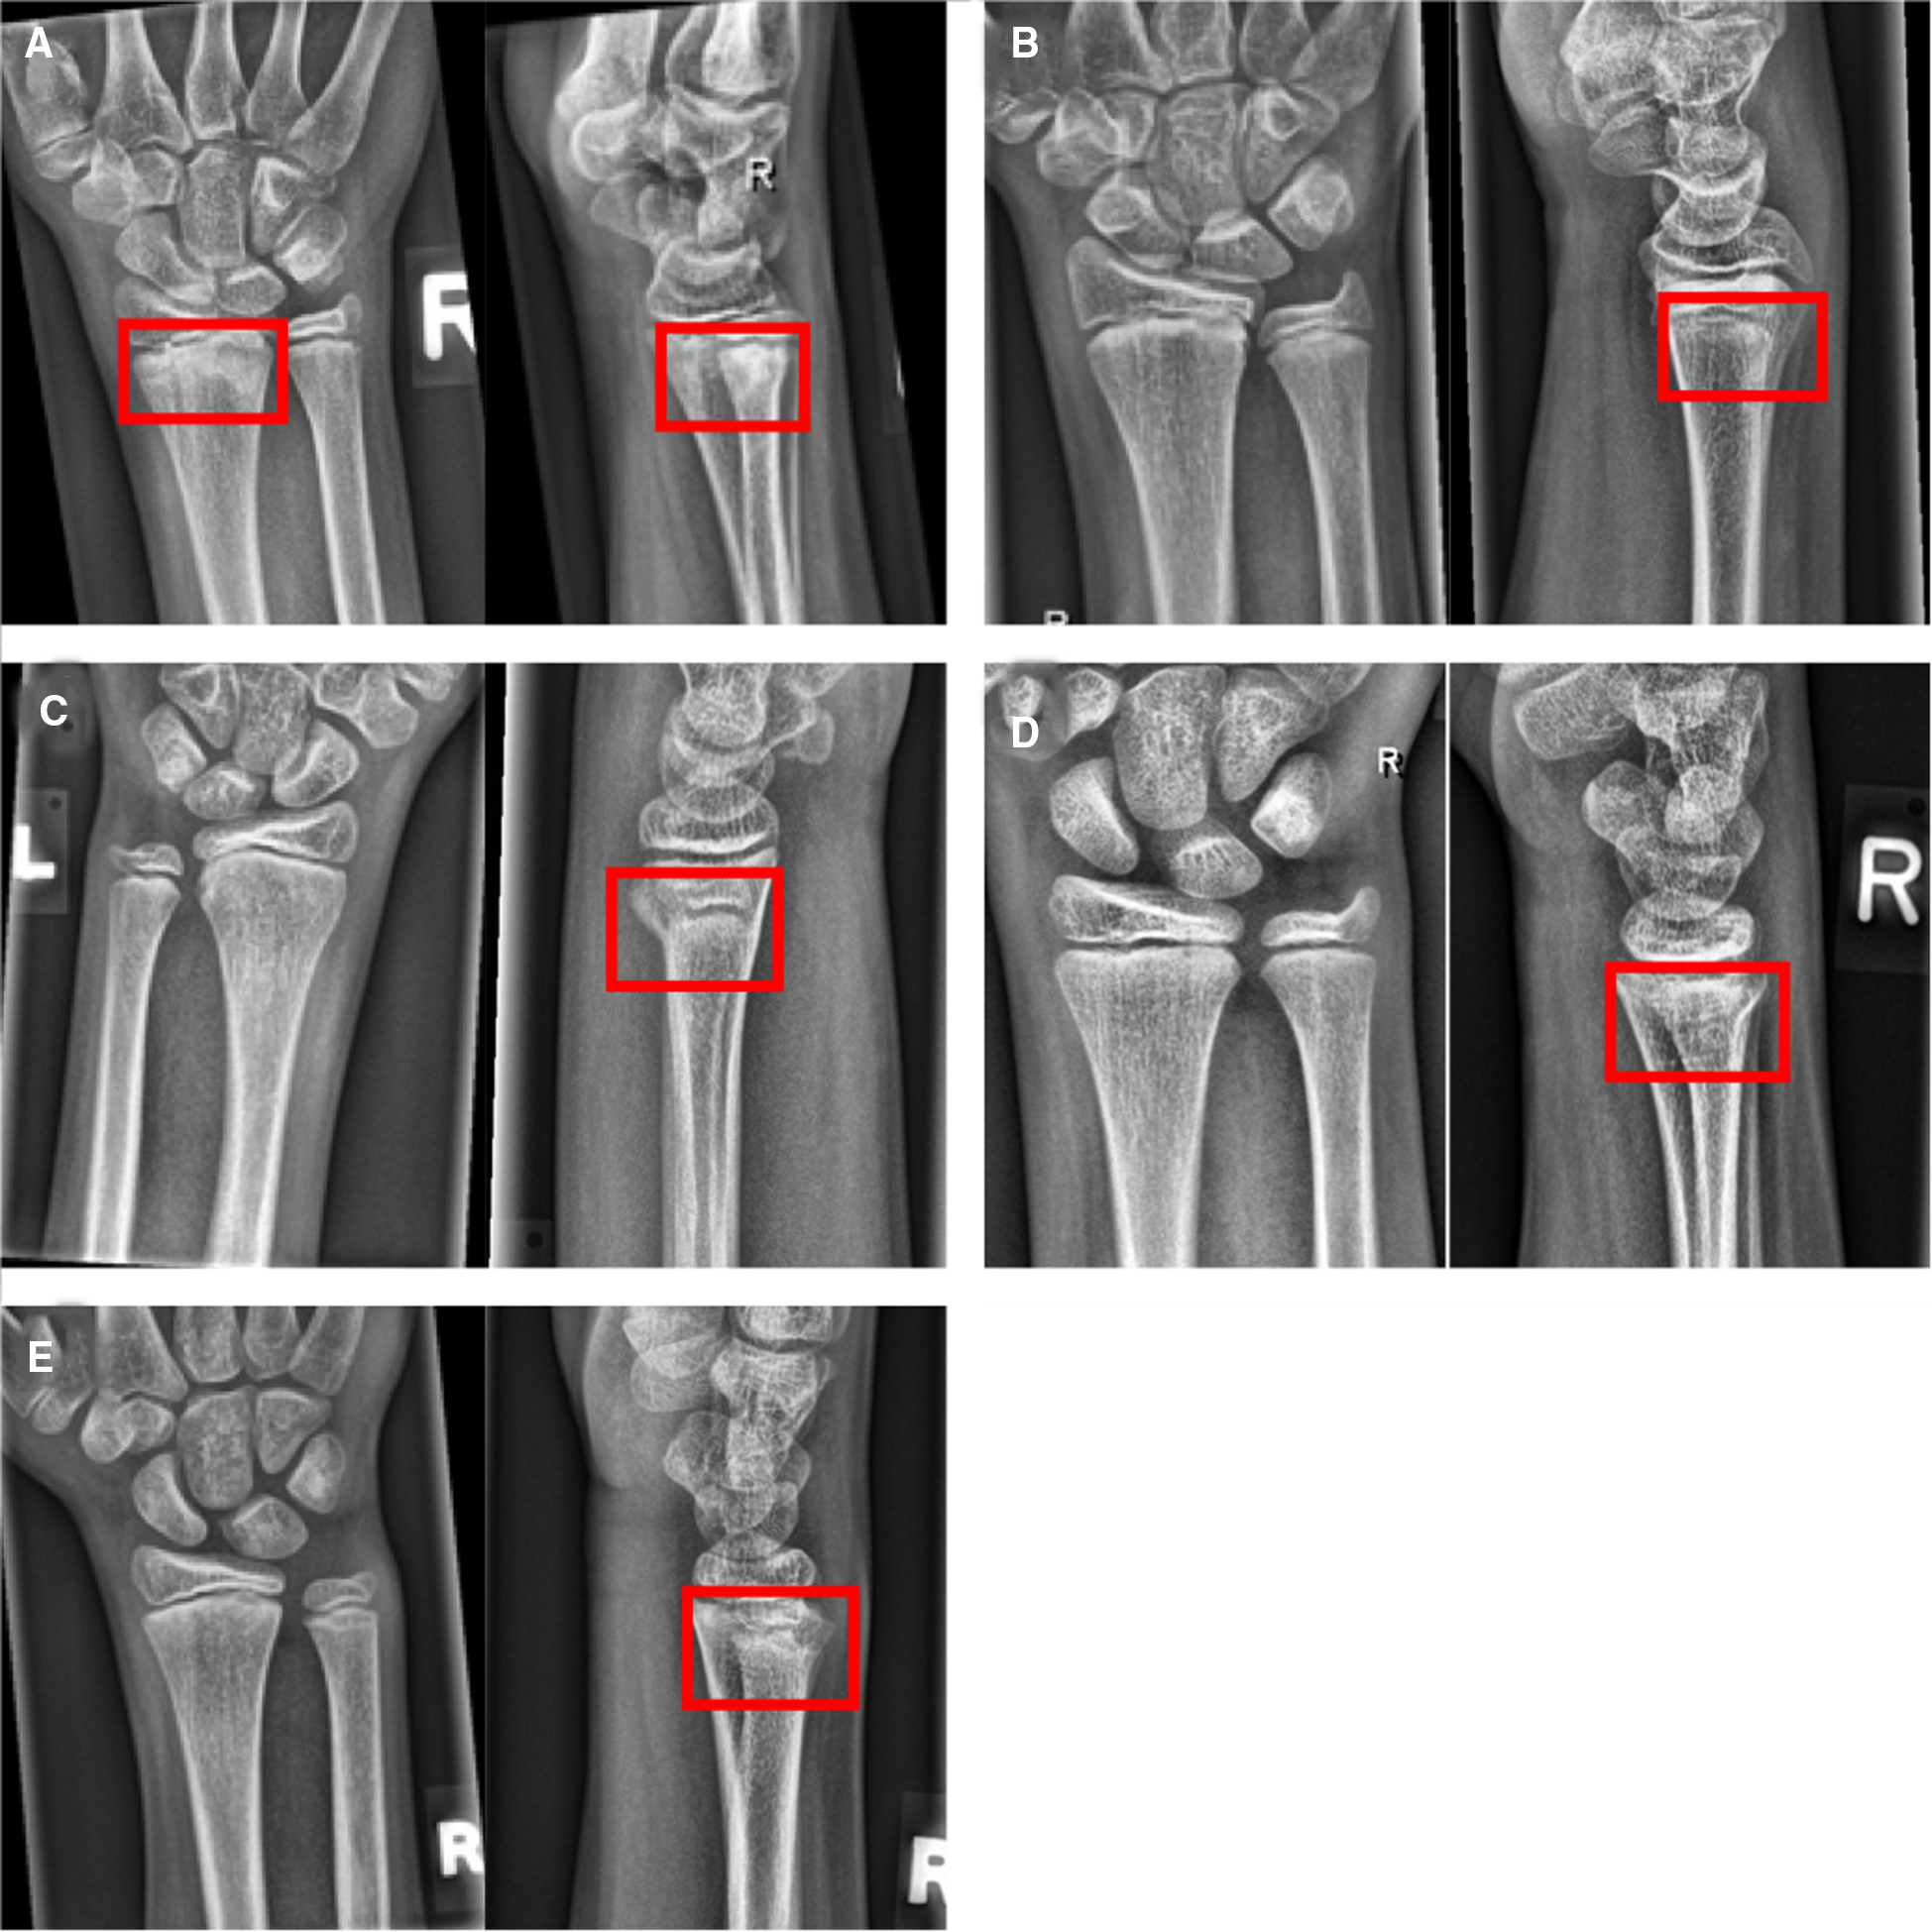

Figure 5

Example studies featuring the most common false negative cases. Lateral projections, if available, have been added to the figure to provide evidence for the presence of the fracture, but have not been part of the test set. (A) Distal radius fracture (red boxes) missed by all CNN models, but seen by 3 of 7 human raters. (B) Subtle dorsal distal radius fracture, missed by all CNN models and human experts. (C–E) Incomplete distal radius fractures missed by all raters but detected by the three CNN models.